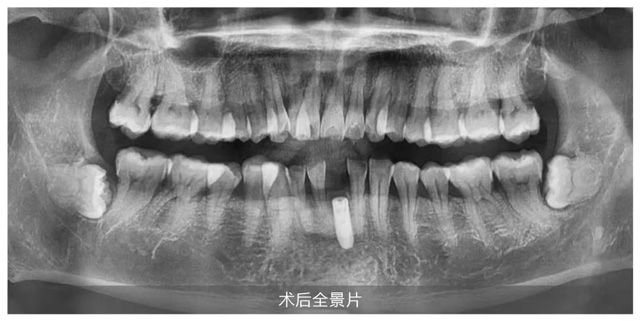

上午10:43時,隨著王鋒總監(jiān)嫻熟實施麻醉、備洞、植入等關(guān)鍵步驟,手術(shù)在短短15分鐘內(nèi)完美收官,全程無痛、出血量少,充分展現(xiàn)了數(shù)字化種植的微創(chuàng)優(yōu)勢。直播顧客王先生十分滿意地表示:“手術(shù)全程不緊張,也沒有痛的感覺。醫(yī)生的技術(shù)和新橋口腔整體服務(wù)都超出了我的期待。”